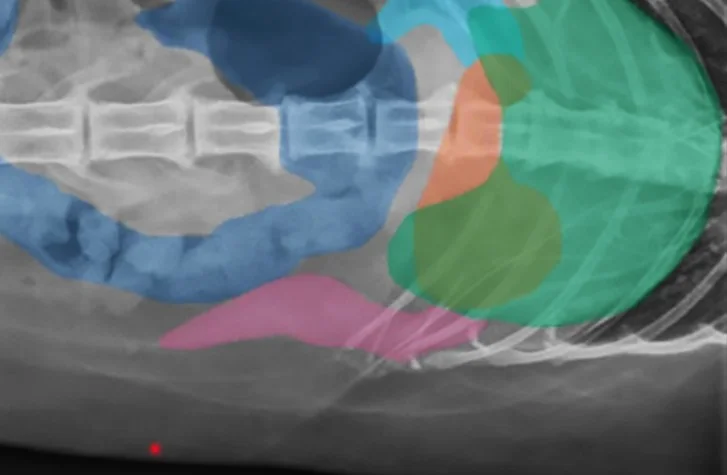

Interactive Radiograph Practice